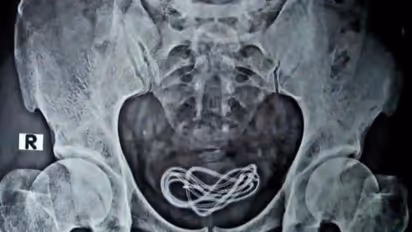

ഓപ്പറേഷൻ ടേബിളിൽ എക്സ്-റേ പരിശോധന നടത്തിയപ്പോൾ യുവാവിന്റെ മൂത്രസഞ്ചിയിലാണ് കേബിൾ ഉള്ളതെന്ന് കണ്ടെത്തി. ഓപ്പറേഷനിലൂടെ കേബിൾ നീക്കുകയും ചെയ്തു. യുവാവ് ഇപ്പോൾ സുഖംപ്രാപിച്ച് വരികയാണെന്നും ഡോക്ടർ പറഞ്ഞു.